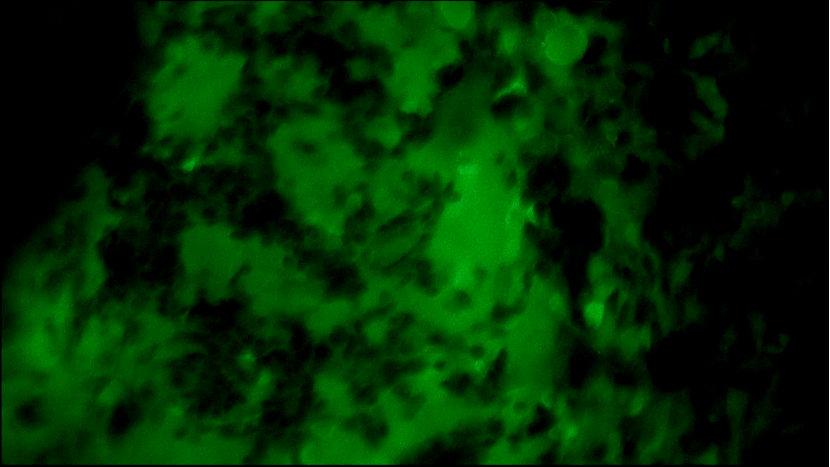

术中EndoSCell®细胞图像如下:

右乳肿物:细胞核体积较大,大大小小形态不一,且细胞核密度高。

左乳肿物:部分区域细胞核密集,分布不均,形态异常。